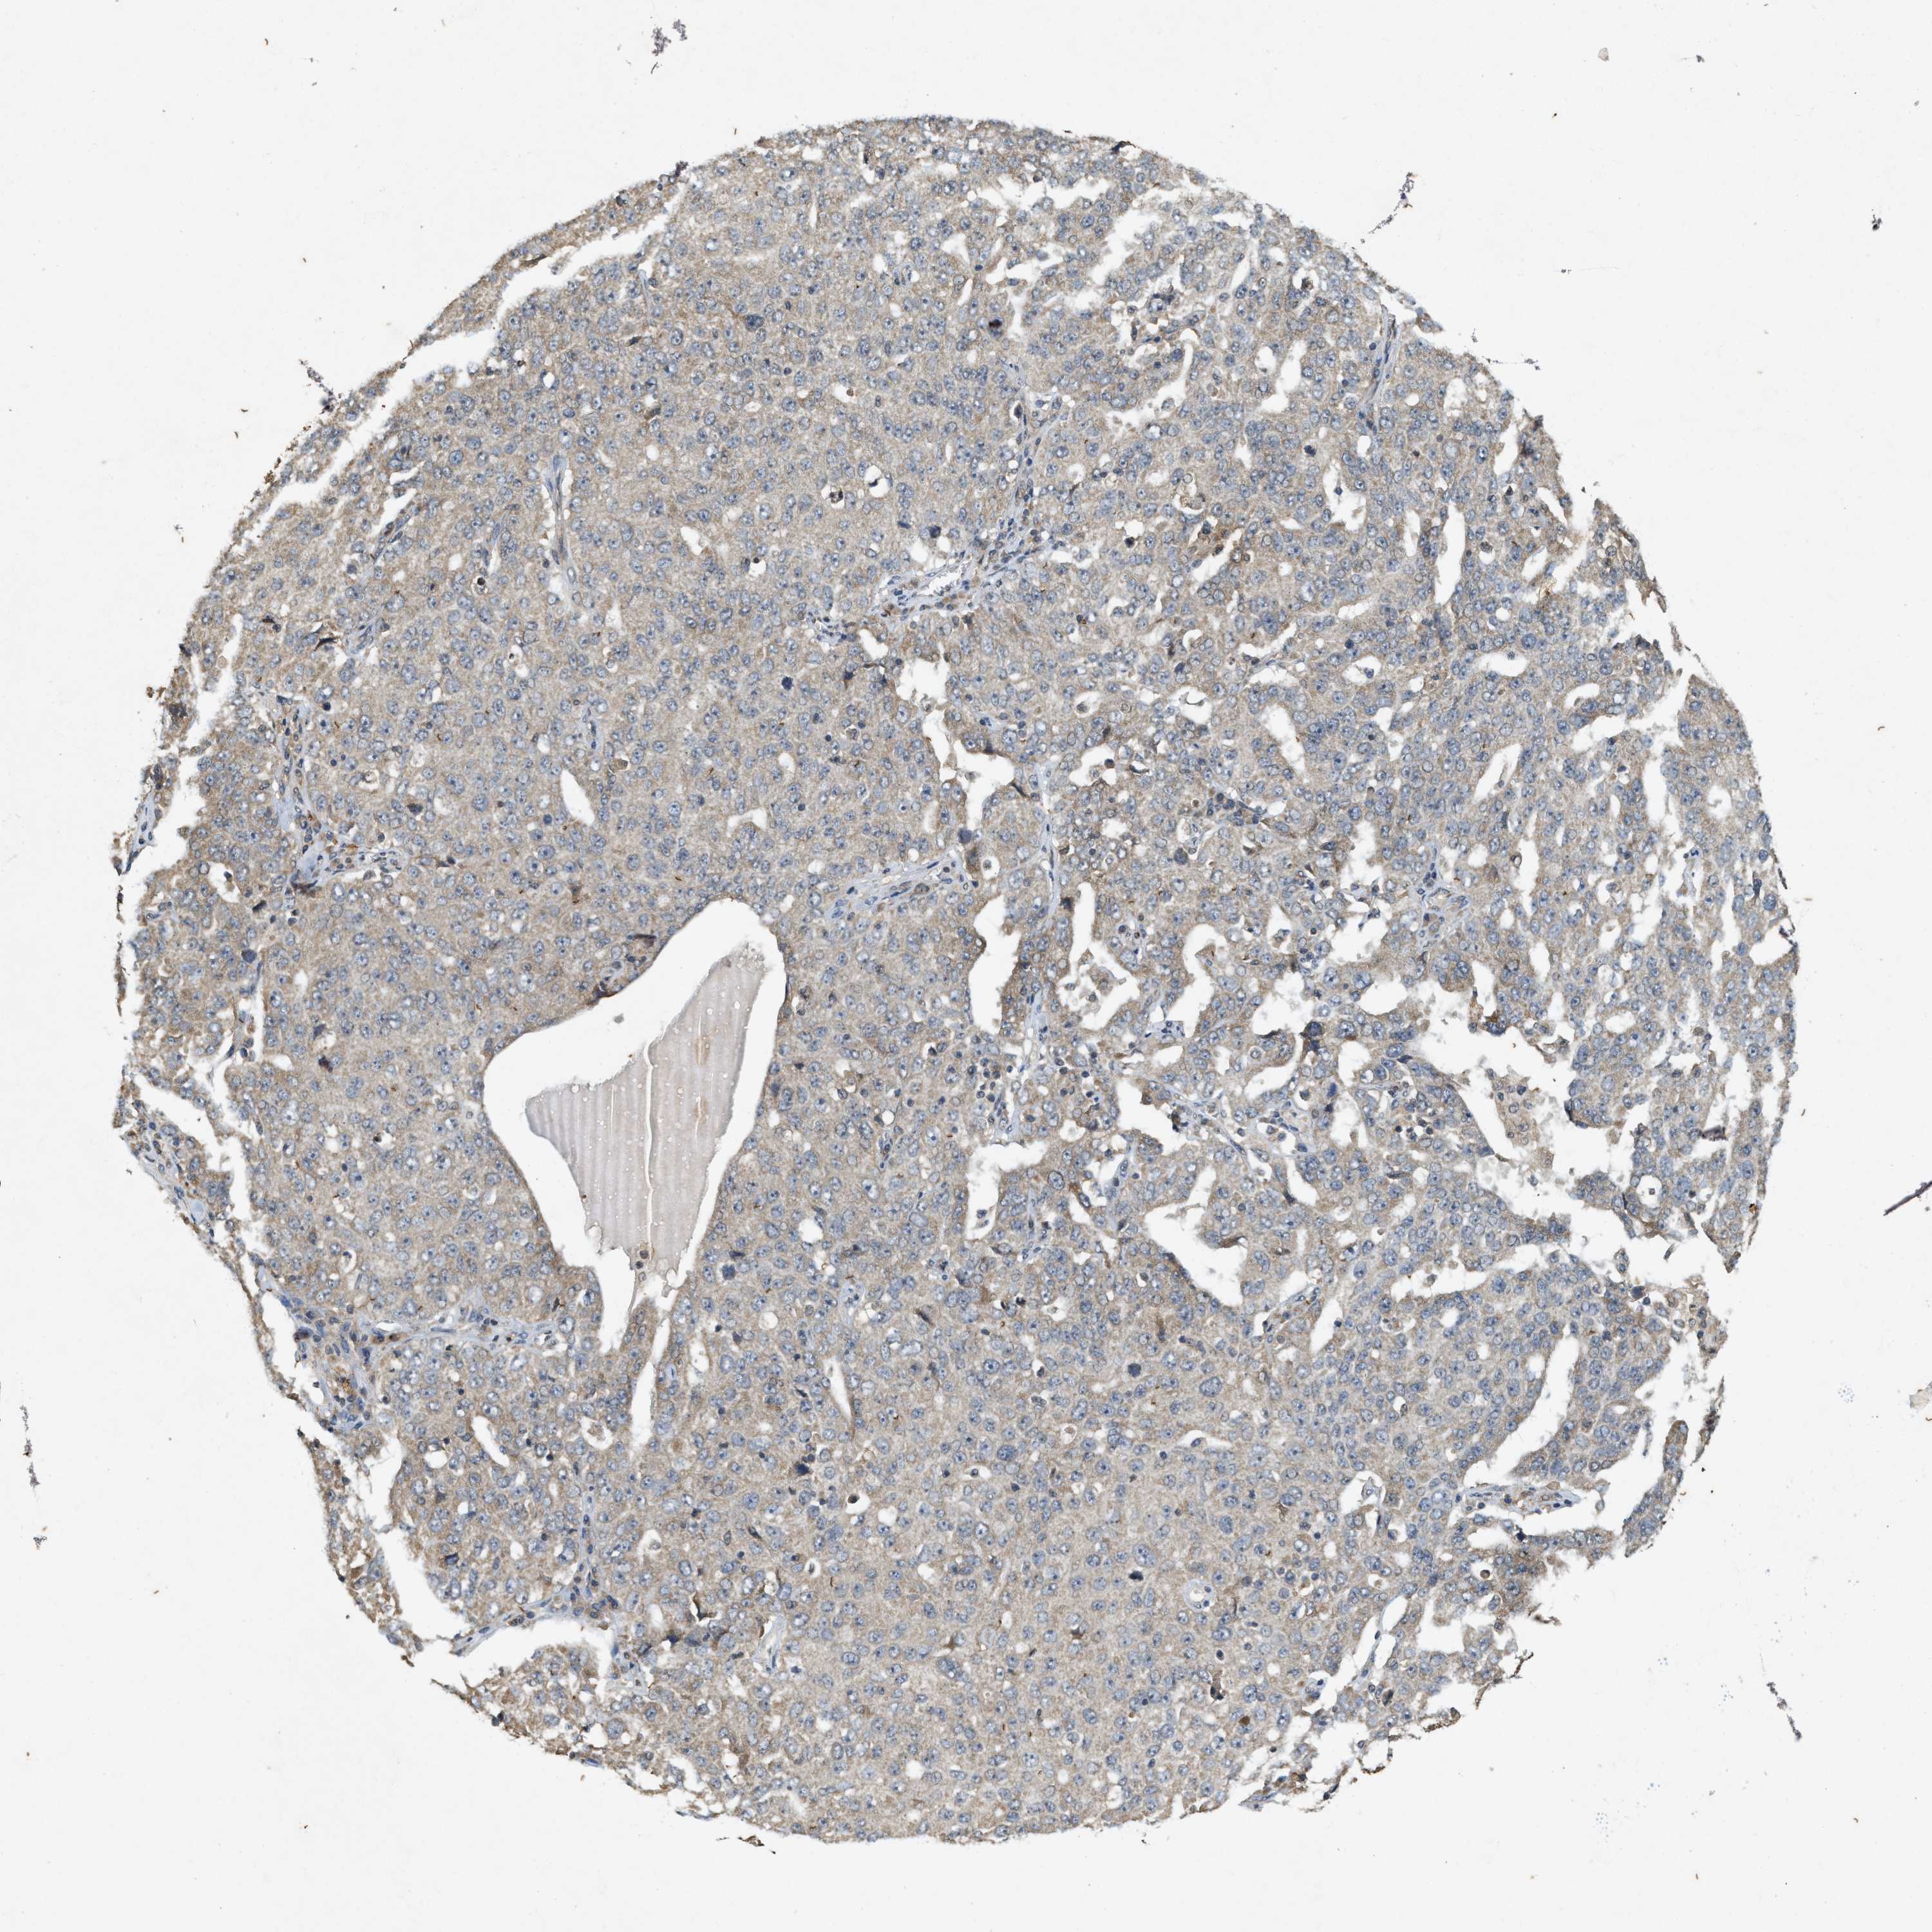

OVARIAN CANCER - Protein expressioni

A mouse-over function shows sample information and annotation data. Click on an image to view it in a full screen mode. Samples can be filtered based on level of antibody staining by selecting one or several of the following categories: high, medium, low and not detected. The assay and annotation is described here.

Note that samples used for immunohistochemistry by the Human Protein Atlas do not correspond to samples in the TCGA dataset.

Antibody stainingi

Antibody staining in the annotated cell types in the current human tissue is reported as not detected, low, medium, or high, based on conventional immunohistochemistry profiling in selected tissues. This score is based on the combination of the staining intensity and fraction of stained cells.

Each image is clickable and will lead to virtual microscopy that enables deeper exploration of all samples and also displays staining intensity scores, fraction scores and subcellular localization as well as patient and tissue information for each sample.

Antibody HPA058432

Antibody CAB022079

Cystadenocarcinoma, serous, NOS

Cystadenocarcinoma, mucinous, NOS

Adenocarcinoma, NOS

Carcinoma, endometroid

Carcinoma, NOS